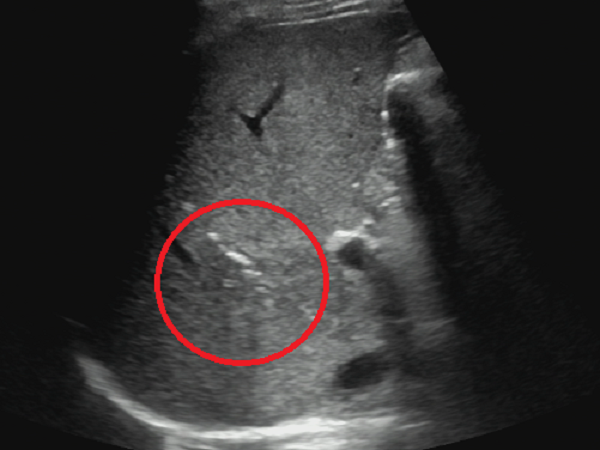

患者于置管引流术后4天复查,右肝前叶上段脓肿基本引流干净(图5)。

图5 红色圆圈处所示脓肿基本引流干净